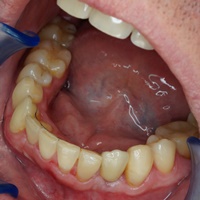

Odbudowa kosci wyrostka zębodołowego żuchwy, odbudowa dziąsła, wydłużenie koron klinicznych górnych przedtrzonowców, implantacja.